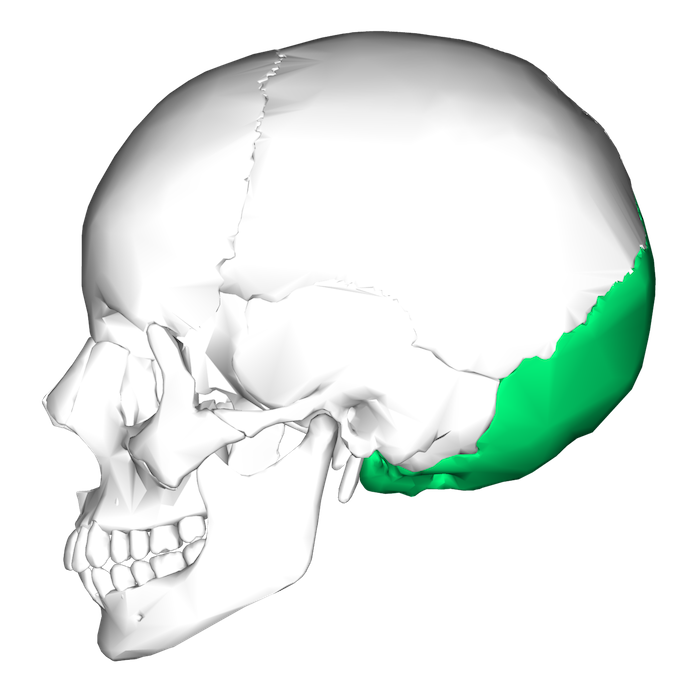

L’osso occipitale (in verde) in una visualizzazione laterale del cranio (Wikimedia)

Nell’area della nuca, più precisamente in corrispondenza dell’osso occipitale, ci sono mediamente tra le 65 e le 85 unità follicolari per centimetro quadrato, cioè gruppetti di 1-4 capelli che originano dai follicoli sottostanti. La densità varia a seconda delle persone e deve essere valutata con attenzione, prima di procedere all’asportazione delle unità follicolari che saranno poi trapiantate in altre aree del capo.

Con le nuove tecniche si cerca di non superare la rimozione di 15-20 unità follicolari per centimetro quadrato, per evitare il rischio di un eccessivo diradamento dei capelli nell’area occipitale, che diventerebbe poi evidente: il classico caso in cui per risolvere un problema se ne crea un altro dello stesso tipo. In mancanza di capelli anche nell’area occipitale, viene valutata la possibilità di utilizzare peli presenti in altre aree del corpo.